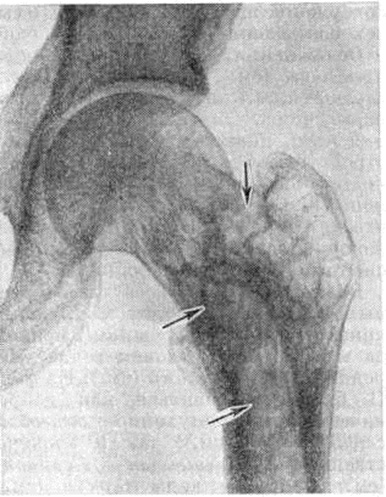

Изменённые трубчатые кости утолщаются, искривляются, изгиб их иногда сочетается со скручиванием по оси (рисунок 5). Поверхность костей становится шероховатой, с отверстиями от мелких кровеносных сосудов. Корковое вещество расширяется, утрачивает компактность, приобретает неравномерно спонгиозированный вид (рисунок 6). Костномозговой канал сужен вплоть до облитерации. На продольных распилах костей выявляются мелкоячеистые и груботрабекулярные структуры (рентгенологически — «ланцетовидное» расслоение, разволокнение). Изменения чаще возникают в диафизах, распространяясь по длиннику кости, захватывают эпифизы. Хрящи суставов не изменяются.

Ранние этапы болезни рентгенологически характеризуются изменениями внутренней архитектоники кости, затем к ним присоединяются утолщение и деформация кости. Наиболее характерна для Педжета болезнь видимая на снимках груботрабекулярная перестройка костной структуры. Костные перекладины утолщаются, группируются в пучки, вследствие чего вся структура кости приобретает грубый вид, ячейки между костными перекладинами становятся крупными, неправильной формы, костные перекладины в основном сохраняют свою функциональный направленность (рисунок 9—11). В процесс перестройки вовлекается и корковое вещество, которое приобретает волокнистый вид; в дальнейшем граница между корковым и губчатым веществом вовсе теряется, кость на уровне поражения утолщается, деформируется (рисунок 12). Целость контуров кости всегда сохраняется. Утолщение трубчатых костей сочетается с сужением костномозгового канала, а затем и полным его исчезновением. Структура поражённого участка кости по всей его толщине становится одинаковой. Кости черепа могут утолщаться в 2—3 раза. Структура их на рентгенограмме отличается своеобразным хлопьевидным рисунком вследствие неравномерной перестройки с чередованием участков уплотнения и разрежения костного вещества. В позвоночнике, как правило, поражается тело позвонка, но процесс перестройки может распространиться и на дугу. Структура позвонка становится грубой, крупноячеистой, основные пучки балок располагаются по сторонам в виде рамы. Тело позвонка всегда увеличено в боковых и переднезаднем направлениях, высота его снижается, реже остаётся обычной.

Перестраивающиеся длинные трубчатые кости постепенно искривляются, с выпуклой стороны нередко развиваются зоны патологической функциональной перестройки (смотри полный свод знаний: Лоозера зоны), на основе которых возникают характерные так называемый банановые переломы, проходящие поперечно к продольной оси кости и имеющие ровную, иногда изогнутую поверхность (рисунок 13).